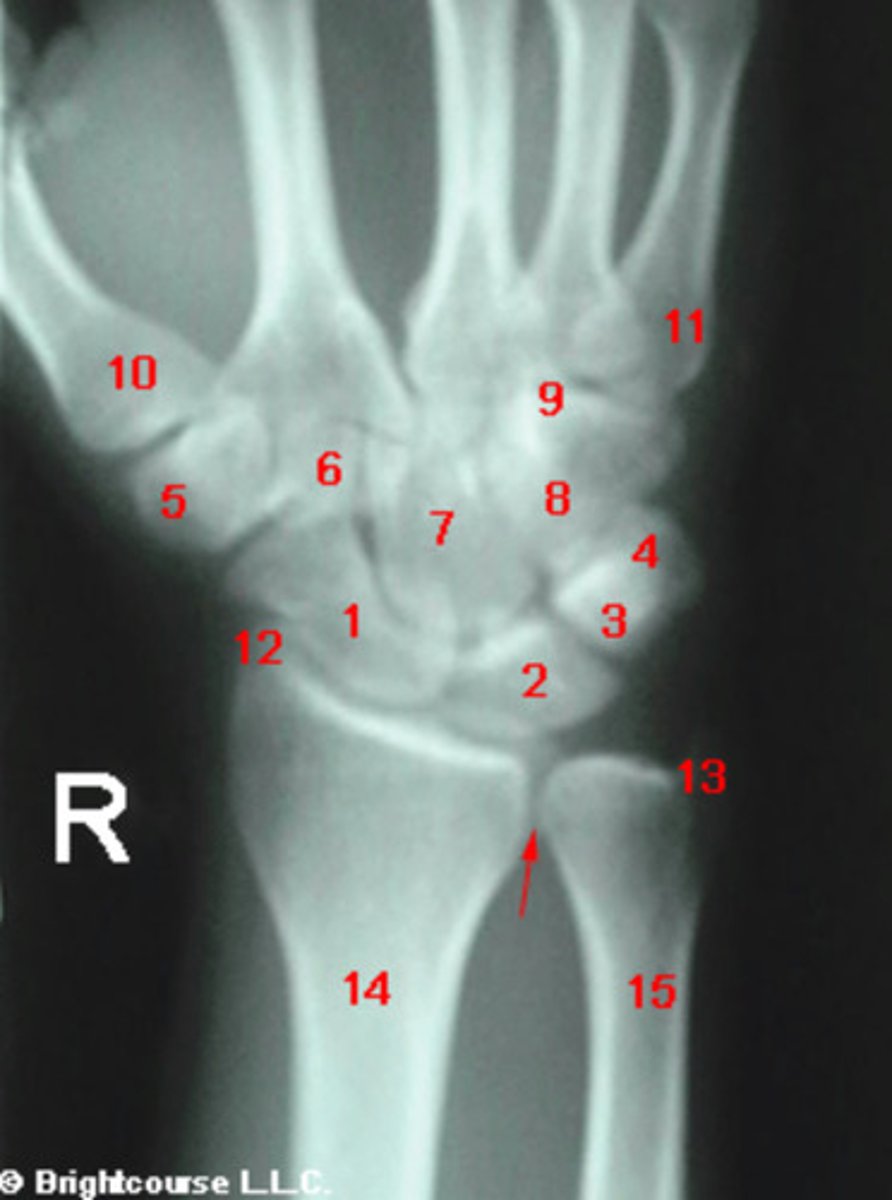

PA, internal oblique, and lateral

What are the standard plain film radiographic projections for the wrist?

What is the normal range for the Carpal angle?

What is the normal range for the radioulnar angle?

What is the normal range for the radius angle?

What conditions can alter the normal carpal alignment?

Negative ulnar variance

An ulnar variance measuring 15mm is considered to be?

Capitate

What structure is indicated by number 7?

Scaphoid

What structure is indicated by number 1?

What structure is indicated by number 2?

What structure is indicated by number 3?

Positive ulnar variance

An ulnar variance measuring 7mm is considered to be what?

What structure is indicated by number 5?

What structure is indicated by number 6?

What structure is indicated by number 8?

What structure is indicated by number 13?

Carpal angle

What angle is being assessed in this image?

3 arcs of carpal alignment

What is being assessed in this image?

Radius angle

Radioulnar angle